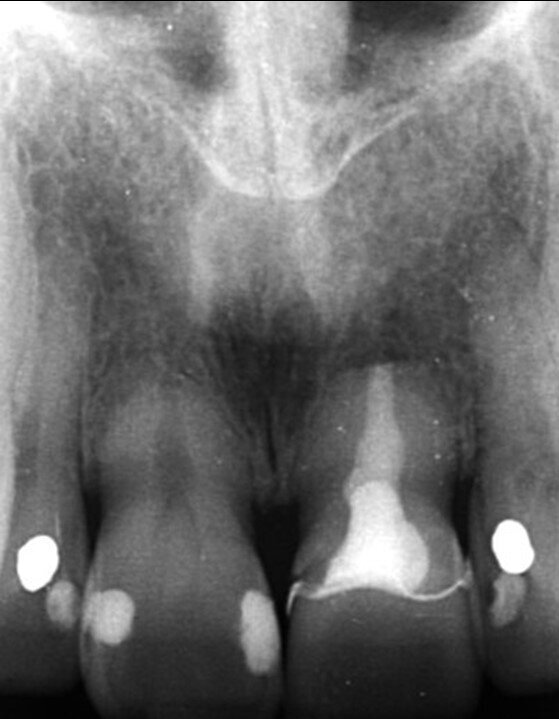

A 53-year-old female patient presented to the office with a fractured left central incisor which had been repeatedly bonded to a ceramic crown (Figs. 1 & 2). Anamneses and examination established good systemic and oral health, a well-balanced occlusion and no smoking habits. Cone beam computed tomography (CBCT) and a periapical radiograph showed external root resorption with very limited insertion into the alveolar bone, insufficient for adequate conventional intra-radicular post placement (Figs. 3 & 4). Considering that the fractured tooth was in the aesthetic zone, the patient requested restoration in the safest and fastest way possible.

Fig. 3: Pre-op periapical radiograph.